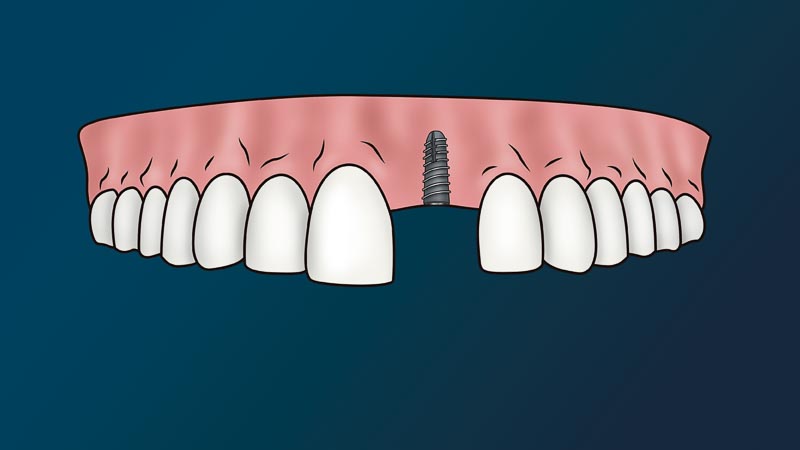

What is the Dental Implant Process in Mexico?

The dentist will attach to your jaw a metal root (implant) and place on top a fake tooth (crown). We call this procedure, a dental implant. Since this procedure is non-life threatening and non-essential to one’s immediate health, it considered a cosmetic procedure. In other words, medical or dental insurance policies don’t cover this procedure.